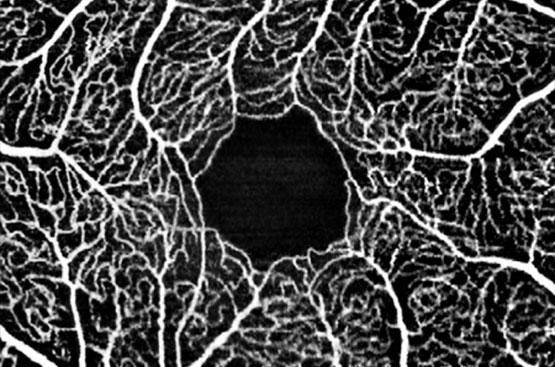

OCT-Angiografia (Angio-OCT)

Rendering HD della circolazione maculare per screening e prevenzione della maculopatia e studio delle patologie vascolari e delle occlusioni arteriose e venose